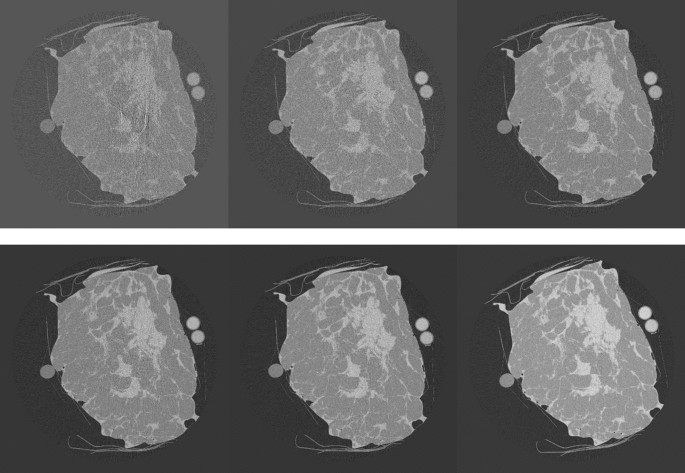

For the T3 tissue sample, the dependence of CNR on MGD was evaluated at 28 keV. Images were acquired at 1, 2.5, 5, 7.5 10 and 20 mGy. The reconstructed slices on which CNR was calculated for the different doses are reported in Fig. 9.

For this phantom the used MGDs were higher. Hence, as expected, CNR shows a behavior proportional to the square root of the number of counts, also for the lowest evaluated doses. In these cases (in particular 2.5 and 1 mGy), the percentage of zero-counting pixels is quite relevant (25% and 56%, respectively).